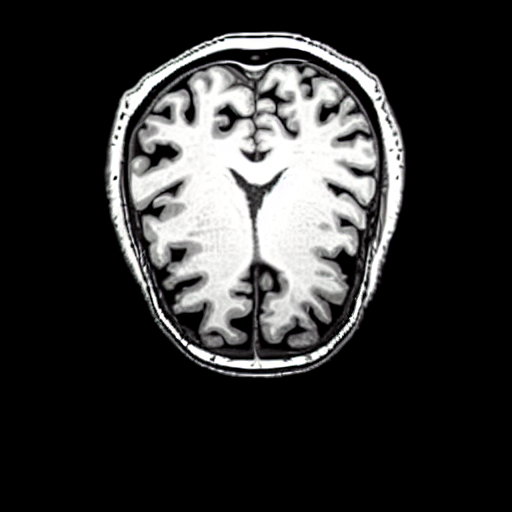

We present the results of conditional medical image generation with and without our proposed method LD, in Tab. 1, and Fig. 5. In Fig. 4, we show examples of brain MR images generated by the different methods combined with LD for two different classes of cognitively normal (CN) and Alzheimer’s disease (AD). The results were obtained by fine-tuning the corresponding method on the medical data with LD. As shown in Fig. 4, the samples generated through Custom Diffusion tuning are realistically looking while understanding the difference between CN and AD brain properly, which other methods failed at. Textual inversion seems to understand the concept but fails to understand the brain structure properly. Quantitative results on the performance of all our methods are presented in Tab. 1. Qualitative results on the CheXpert [19] dataset, along with a user study and ablation of different parameters, optimization algorithm, and more, are included in the supplementary material.

Qualitatively, Fig. 5 shows a significant improvement of the visual realism across all methods when using a drift of . The background is consistently black as in real brain MR images; the shape of the brain becomes more realistic, and the white and gray matter structure improves. For an analytical evaluation, we calculated the FID between our test data and 200 synthetically generated images from each method (100 CN, 100 AD). The results in Tab. 1 demonstrate that LD improves the ability of the model to generate realistic MRI slices for both healthy brains and brains with Alzheimer’s disease. For this reason, all following experiments were done with LD.